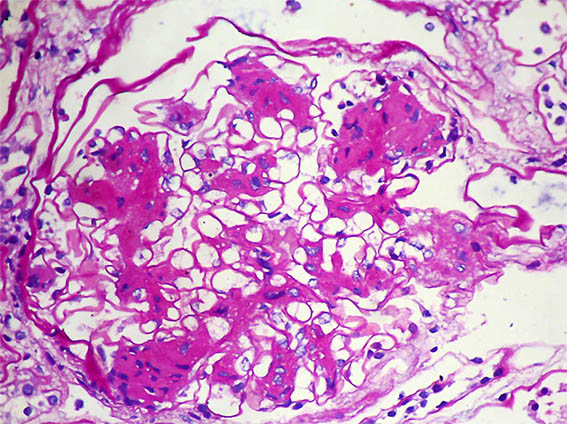

Figura 1. PAS, X400. Nódulos mesangiales.